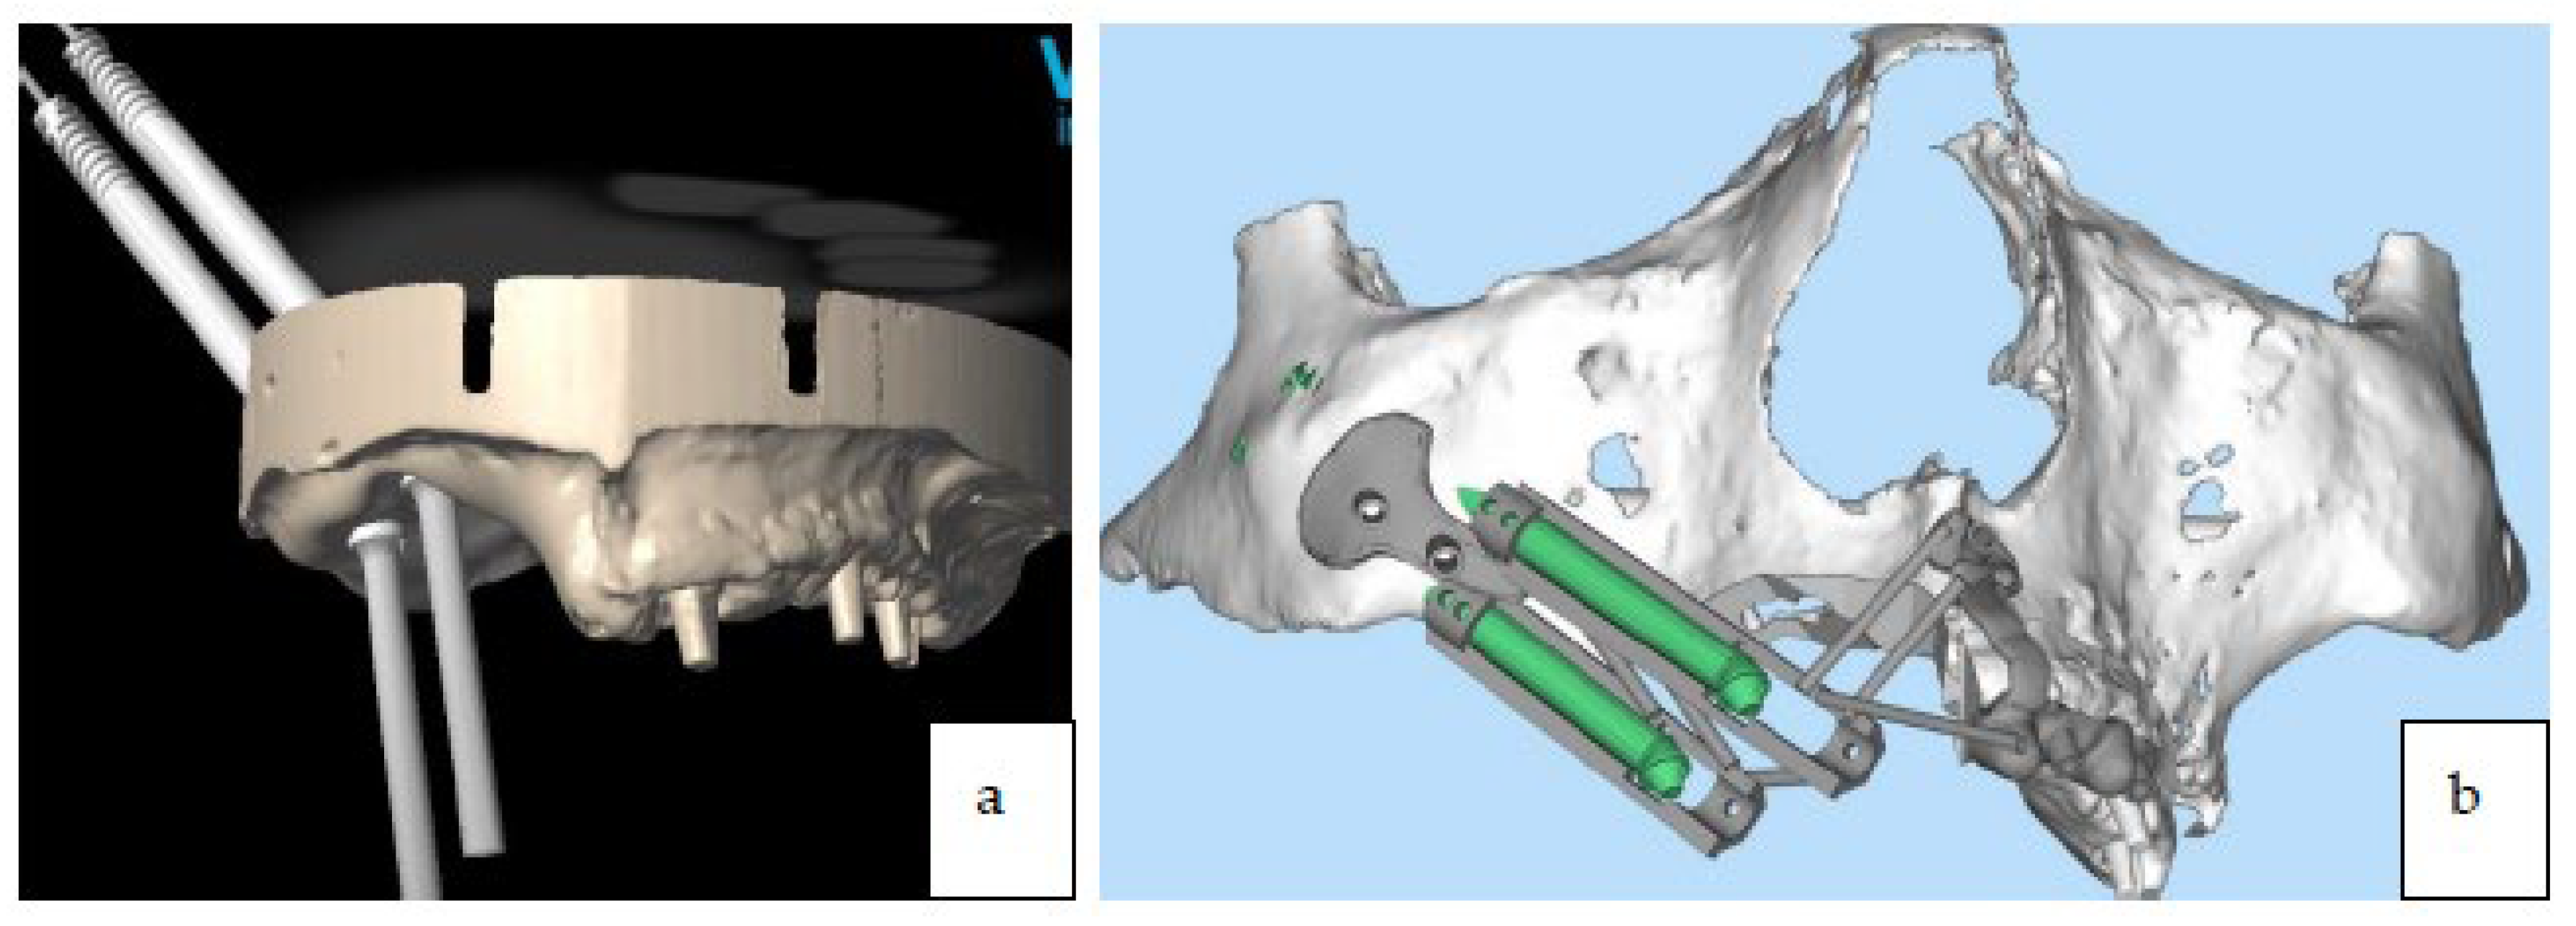

3.4. Preoperative Digital Planning

4. Surgical Technique